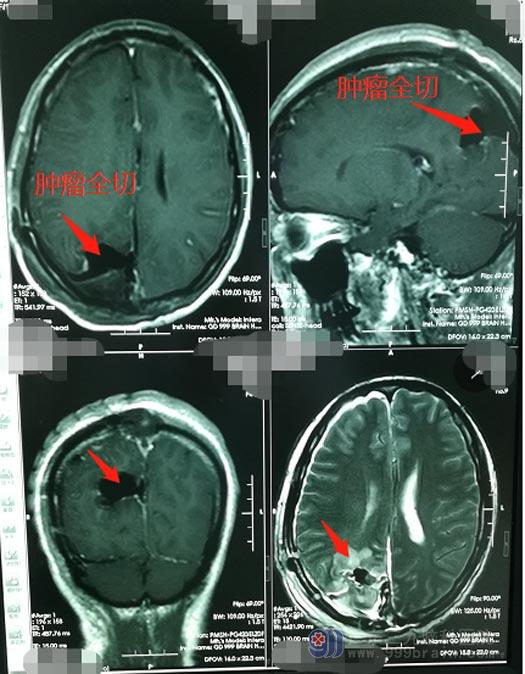

手术中稍有不慎,罗女士就会有生命危险,但不进行手术,颅内肿瘤还会继续增长,造成更加严重的危害。鲁明和团队一起充分评估手术风险并且制定了缜密的手术方案,在全麻下为罗女士施行“右侧顶部镰窦脑膜瘤切除术”,术中彻底切除窦内外肿瘤,无残留。罗女士术后恢复良好,手脚活动有力,无阳性体征,她和家人心中悬着的大石总算是落下了下来。